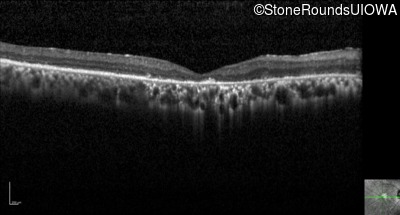

Optical Coherence Tomography - Right - 20/1250 sc

Exemplar / OCT Stack

OCT Stack